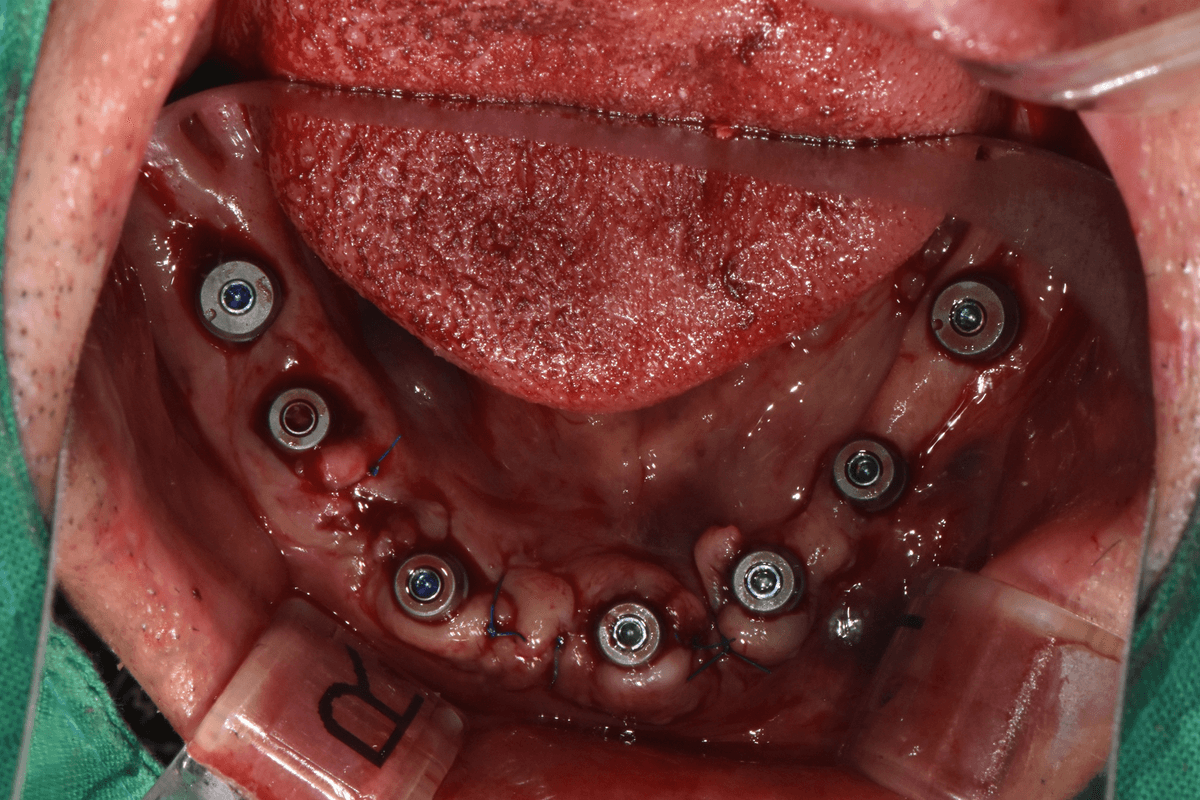

Flapless Implant Surgery

Immediately after flapless implant surgery

Placed through a small hole without gum incision,

resulting in minimal bleeding and swelling

01Flapless Implant

• • Placement through small hole without incision

• • Minimized bleeding, pain, and swelling

• • Quick return to daily life after surgery